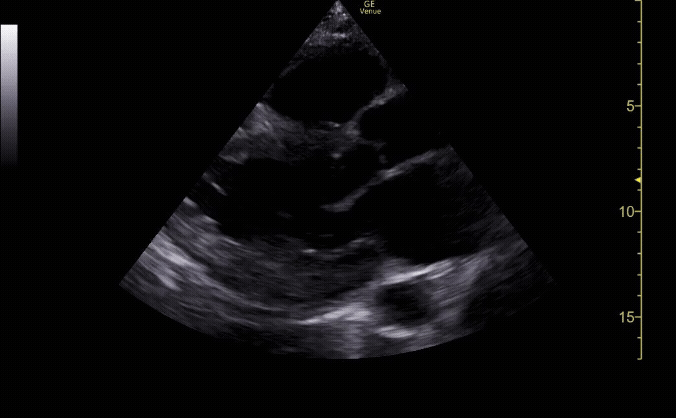

Subxiphoid view showing the liver, right ventricle, right atrium, left atrium, and left ventricle.

c/o Kyle Ackerman, MD